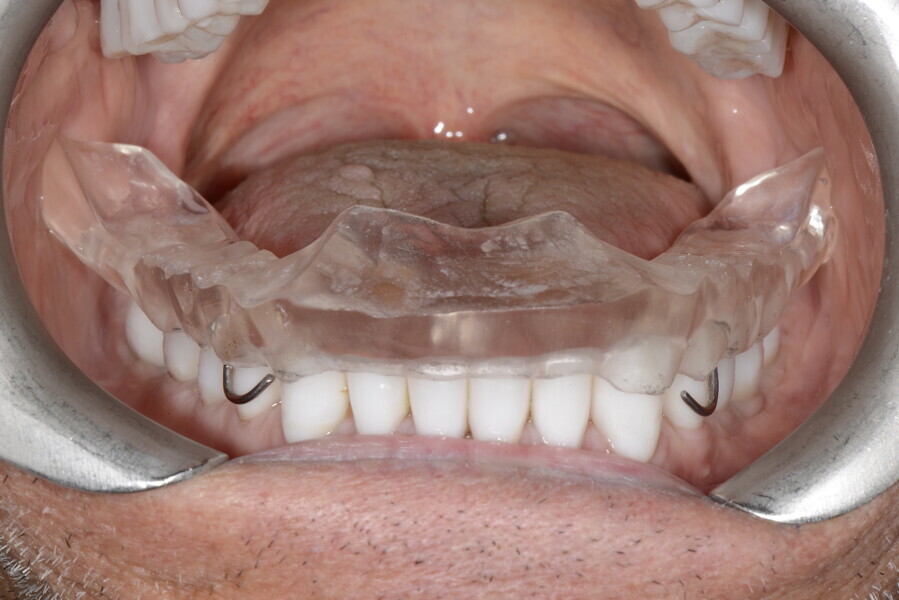

2. muscular deconditioning and TMJ relief with a Ri.P.A.Ra. device;37

This patient, like all patients requiring interdisciplinary rehabilitation, had to first undergo periodontal treatment and caries restoration (Fig. 17). At the same time, it was important to rehabilitate swallowing with Froggymouth and relax the masticatory muscles and relieve the TMJs with an occlusal device. We could then study the orthodontic treatment plan using Invisalign ClinCheck (Align Technology) and showed the treatment plan to the interdisciplinary team and to the patient (Fig. 18). We were then able to create the correct sequence of orthodontic treatment, bone augmentation and implant surgery needed for the posterior edentulous spaces.

For maintenance purposes, after prosthetic finalisation, the patient was to carry on with the Froggymouth therapy and to use the Ri.P.A.Ra. for physiotherapeutic exercises and mastication training (Fig. 28). It was strongly recommended that the patient wear a mandibular occlusal splint during sleep. This occlusal splint was designed with disclusion guides to advance the mandible and ensure balanced contralateral support (Fig. 29).11, 39 We achieved an aesthetic appearance with adequate inter-arch coherence and a better cephalometric result (Figs. 30 & 31).

To monitor patient progress and the biological situation over time, we conducted periodic examination using radiographs and clinical assessment. Additionally, we evaluated the functional behaviour of the tongue and mastication using the swallowing analysis mentioned earlier and the G-test (chewing gum mastication test; Fig. 32).26